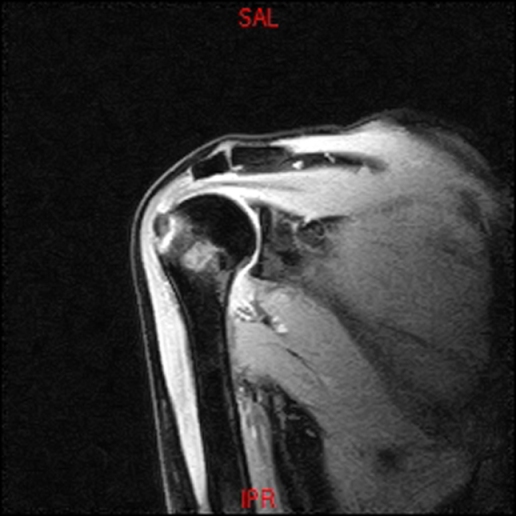

• RESONANCIA PATOLÓGICA DE HOMBRO - FRACTURA TROQUITER -  COR T1

• RESONANCIA PATOLÓGICA DE HOMBRO - FRACTURA TROQUITER Y EDEMA OSEO -  COR T2 WF